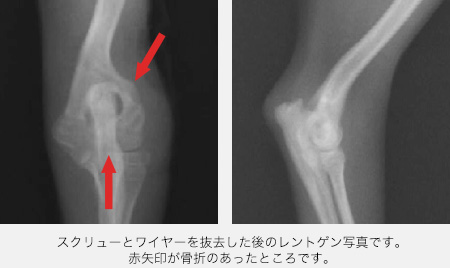

術後は少しずつ足を使うようになり、2ヶ月ほどたって骨が癒合し、スクリューとワイヤーを全て抜去しました。

早めに治療できたため、足の長さは左右差なく成長することができました。